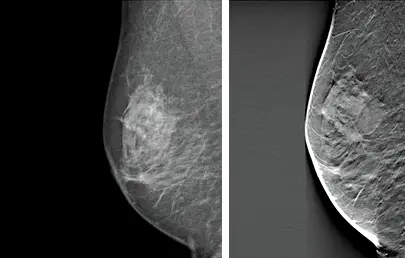

Cancer visible on the right 3D mammogram but not the left 2D mammogram.

In the mammogram image, the glandular and fibrous tissues are white, while the fat is black. However, abnormalities that signal the presence of cancer also appear white and can be mistaken as normal glandular breast tissue, particularly if the breasts are dense.